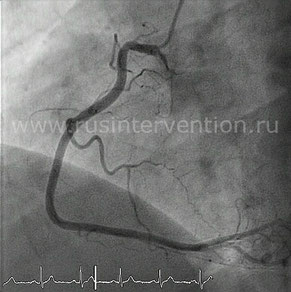

Во время контрастирования коронарных артерий выполняется запись исследования. Выглядит это следующим образом:

Ангиография левой коронарной артерии